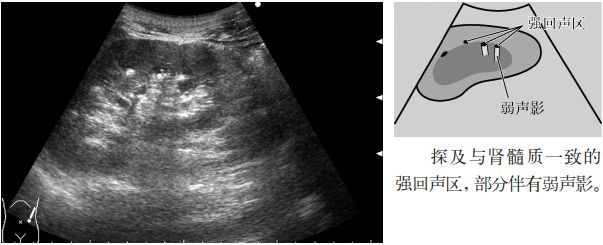

4.肾实质内的高回声(肾小管酸中毒或海绵肾所致的钙化)。

图7 痛风肾